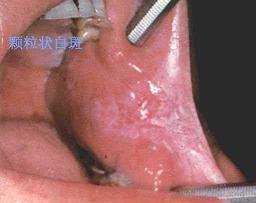

口腔粘膜病组图